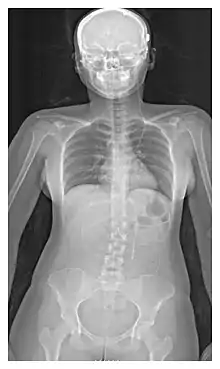

A cerebral shunt is a device permanently implanted inside the head and body to drain excess fluid away from the brain. They are commonly used to treat hydrocephalus, the swelling of the brain due to excess buildup of cerebrospinal fluid (CSF). If left unchecked, the excess CSF can lead to an increase in intracranial pressure (ICP), which can cause intracranial hematoma, cerebral edema, crushed brain tissue or herniation.[1] The drainage provided by a shunt can alleviate or prevent these problems in patients with hydrocephalus or related diseases.

Shunts come in a variety of forms, but most of them consist of a valve housing connected to a catheter, the lower end of which is usually placed in the peritoneal cavity. The main differences between shunts are usually in the materials used to construct them, the types of valve (if any) used, and whether the valve is programmable or not.[2]